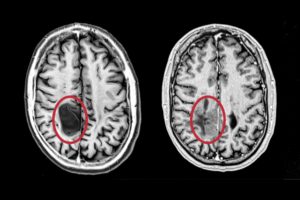

- Brain cancer vs cannabis